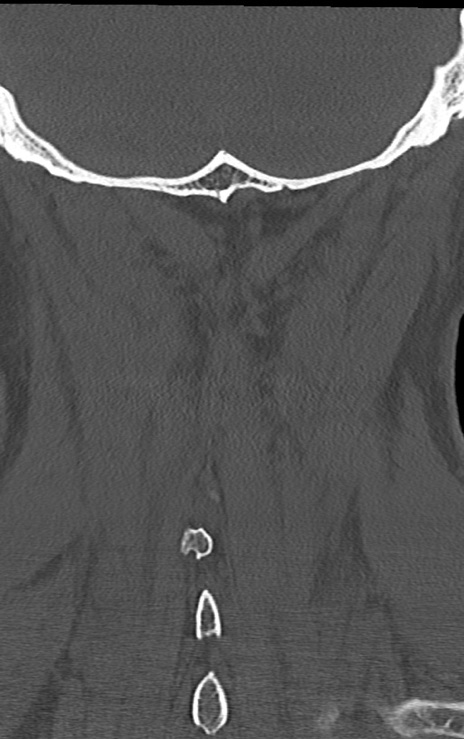

頚椎CT

矢状断像